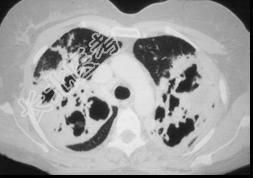

- 单项选择题一养鸽女,48岁, 发热,咳嗽, 咳脓痰带血半月余,请结合CT检查选出最可能的诊断 ( )

A、原发性肺结核

B、肺曲菌病

C、肺癌

D、间质性肺炎

E、支气管扩张